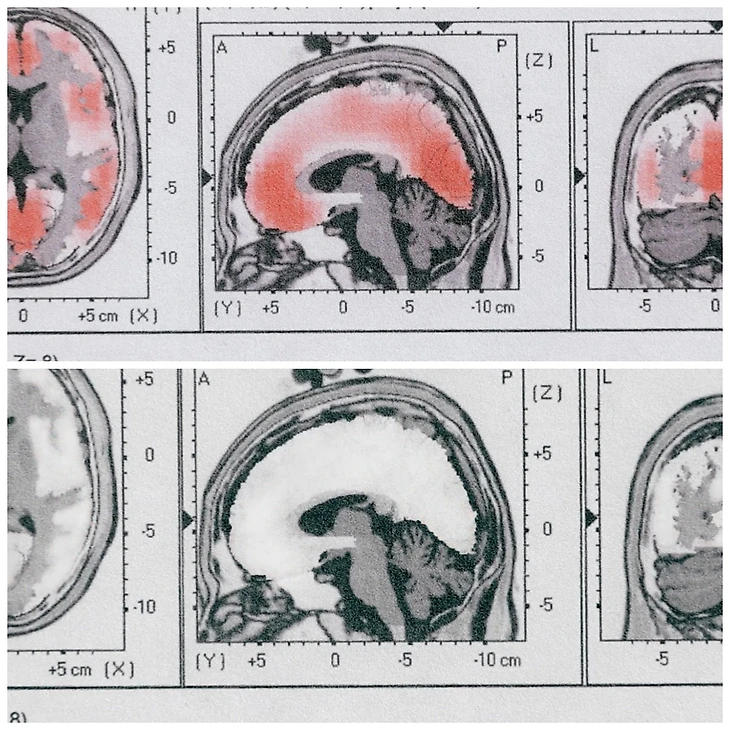

«Я был так близко головой к желобу, что у меня часто были сколы краски и царапины на боку шлема от простого постукивания, проезжая всю трассу. И поэтому, вы знаете, конечно, не попадая в аварию, это просто накапливалось со временем, как снежный ком». — говорит бобслеистка Кристина Смит. Спустя годы после того, как она перестала выступать, Смит обратилась к специалисту, который провел тест под названием количественная электроэнцефалограмма, или КЭЭГ. Прелесть этого метода в том, что он действительно может видеть, где активизируется ваш мозг, не активизируется вообще, или активизируется частично, или активизируется слишком сильно. Когда врачи проанализировали ее результаты, они увидели это.

Грубо говоря, красная штриховка коррелирует с чрезмерной активацией (верхнее фото). В мозге, который не испытал травму, эти области были бы белыми (нижнее фото).